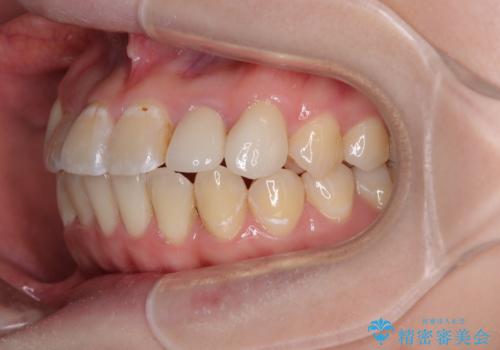

- 上下の歯が非接触であり、八重歯やむし歯を気にして来院された患者様です。

下顎骨の左右偏位はあるものの、上顎骨幅が相対的に狭い状態であったので、奥歯の咬み合わせが非常に乱れていました。

急速拡大が奏効し、非抜歯矯正にて八重歯を解決することができました。